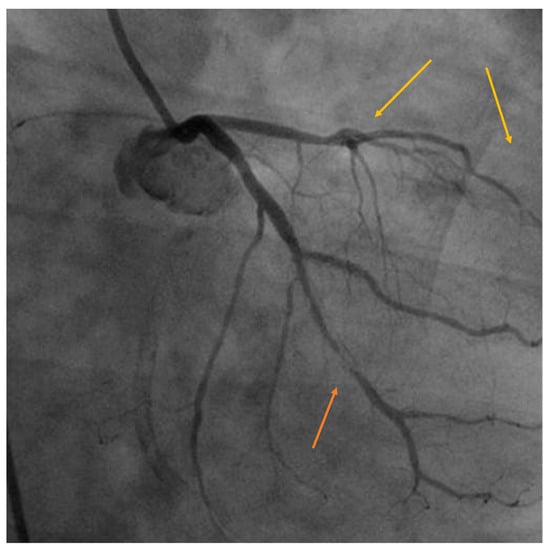

The endothelial cell is highly radiosensitive, and doses higher than 2 Gy can trigger inflammatory cascades that favor atherosclerosis. When combined with the prothrombotic condition of cancer, it can lead to conditions such as angina, acute coronary syndrome, myocardial infarction, malignant arrhythmias, and death. Coronary involvement is anatomically correlated with the site of radiation, and in left BC, lesions are most commonly found at the level of the left main coronary artery, the ostia, or the anterior descending artery in the mid and distal segments, the diagonal branches, and in the proximal segment of the right coronary artery. Atheromatous plaques tend to be longer, of tubular appearance, soft, with more fibrotic than lipidic contents, and frequently present intimal hyperplasia. Figure 3 graphically illustrates the late coronary disease in a 56-year-old patient without basal cardiovascular risk factors diagnosed with triple-negative breast cancer and treated with anthracyclines, paclitaxel, and RT (45 Gy) to the whole breast. It is complex to identify the ultimate cause of this patient’s coronary artery disease because RT has a synergistic effect with chemotherapy, which itself has a proven coronary deleterious effect, but what is striking, in this case, is the distribution of the lesions, both in length and location, matching precisely with the irradiated area. Although its therapeutic management is the same as for conventional treatment (in patients with no prior RT), revascularization should be evaluated in the presence of acute coronary syndrome or myocardial infarction [9,20,22]. Whereas the link between coronary artery disease and previous irradiation is well-established, the risk of death has diminished significantly over the years, and long-term follow-up of patients treated with contemporary RT techniques could provide some interesting answers.